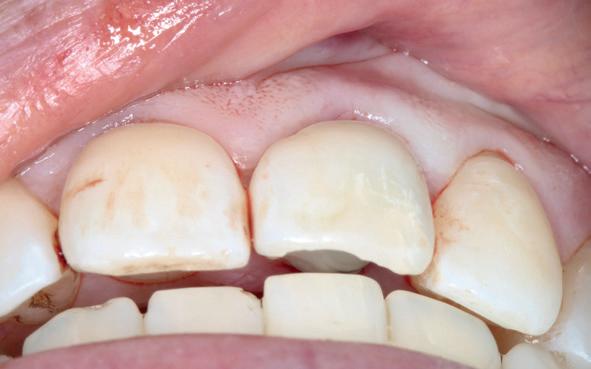

sue-level. Dit naar gelang de locatie in de mond varieert. Voor immediaat implanteren moet er grotere primaire stabiliteit gehaald worden. De implantaten moeten daarvoor langer, agressiever en dikker worden. De vorm van de alveole van het geëxtraheerde element is daarin vaak leidend. We plaatsen implantaten met een afwijkende morfologie, wat niets te maken heeft met het langetermijneffect van de behandeling, maar met hogere initiële stabiliteit. Dus om überhaupt de behandeling te laten slagen, maken we een implantaatkeuze, waar de patiënt niet per se bij gebaat is.

Een veelgebruikt argument voor immediaat implanteren is dat we het omvormen van de alveole willen beperken (en daarmee esthetisch beter uitkomen). Dus niet alleen tijdwinst, maar ook gericht op het voorkomen van het ontstaan van bijvoorbeeld een buccale deuk. We weten uit voldoende literatuur dat die deuk ontstaat door verlies van bundle bone. Het botdeel dat doorbloeding ontvangt vanuit het parodontaal ligament. Met name in het front is dit een veel bepalende factor (afbeelding 1a).

We weten uit meer dan voldoende literatuur van dieren en humane studies dat het resorptieproces in elk geval doorgaat, zonder of met een implantaatplaatsing. Het argument om immediaat te implanteren, zodat we resorptie voorkomen en beter esthetisch uitkomen, is dan ook de eigenlijke kunstfout. De langetermijnresultaten over dit onderwerp zijn dan ook heel erg wisselend en vaak niet ouder dan 10 jaar.

In de zijdelingse delen verwachten we ongeveer 3.5 mm verticaal verlies na extractie van een element. Om dit proces te voorspellen, plaatsen we immediaat geplaatste implantaten om die reden dieper en meer naar linguaal/palatinaal (met bijbehorende risico’s) (afbeelding 2a, 2b).

Daarbij weten we niet waar exact de horizontale en verticale resorptie gaat stoppen. We willen immers kosten wat kost voorkomen dat het ruwe gedeelte van het implantaat onbedekt gaat worden (afbeelding 2c-2f ). Natuurlijk is er 6 mm onder de toekomstige outline van de glazuurcement grens een verwaarloosbaar risico, maar daar had je delayed geplaatste implantaat niet gestaan. Die had slechts 3

mm onder de toekomstige CEJ gestaan. Kortom, we nemen risico’s in de locatie van het implantaat met kans op ruw oppervlakte onbedekt, die niet in het belang van de patiënt zijn.